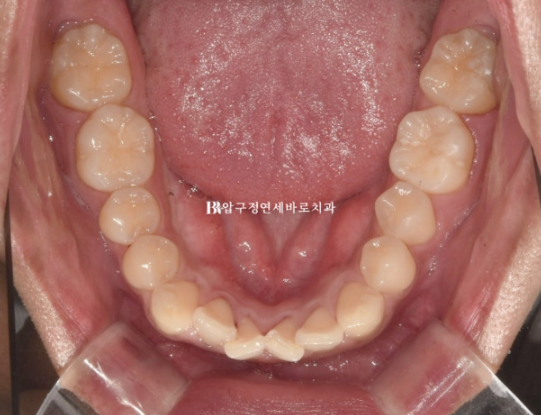

교합면 사진에서 보듯 치아가 입천장으로 들어가 있기 때문입니다.

이렇게 배열에서 벗어나게 나온 영구치를 이소맹출된 치아 라고 합니다.

배열도 가지런해졌고 이소맹출이 되어서 입천장으로 들어가있던 치아도 제자리를 찾았습니다.